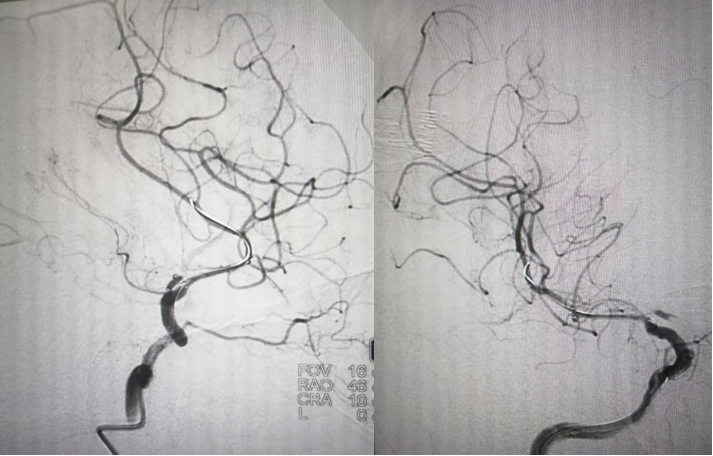

术中造影

DSA(天坛医院-2021.03.17 MCA支架内重度狭窄